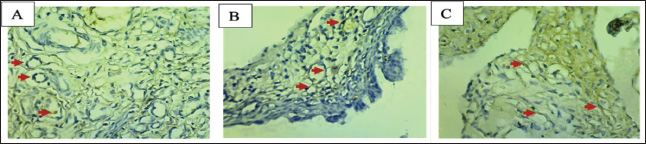

According to the research findings, the negative control group (A) had higher ER-β expression than groups P1 (3.15 mg/kgBB) and P2 (4.72 mg/kgBB) (C). There was a decrease in ER-β in the ovary cells of the group treated with papaya leaf extract (Fig. 2). Table 2 shows the average results of ER-β expression in the ovaries in each group.

Fig. 2. Microscopic view of ER-β expression in ovarian cells using IHC (400×). A: Negative control, B: P1 dose (3.15 mg/kgBW of papaya leaf extract), C: P2 (4.72 mg/kgBW of papaya leaf extract), ↑: Expression of ER-β.

The reduction in ER-β expression observed in treatment groups P1 (3.15 mg/kgBW) and P2 (4.72 mg/kgBW), which received papaya leaf extract, is likely attributed to antiestrogenic of the bioactive compounds present in the extract. The antiestrogenic components in papaya leaves may competitively bind to estrogen receptors, thereby inhibiting the binding of endogenous estrogen. This receptor competition impairs normal estrogen signaling, which is essential for follicular development and reproductive cycle regulation (Nafiu and Rahman, 2015). Antiestrogenic compounds can mimic estrogen structurally but lack the full biological efficacy required to activate receptor-mediated transcription.